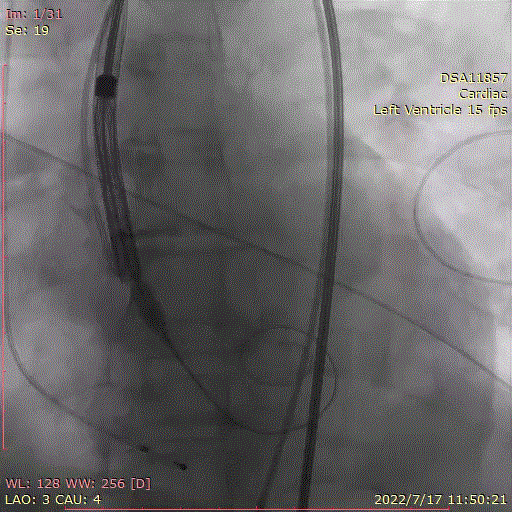

主动脉根部造影示主动脉瓣重度狭窄,采用20mm球囊预扩,有轻微腰征,无造影剂渗漏。

主动脉根部造影

20mm球囊预扩张